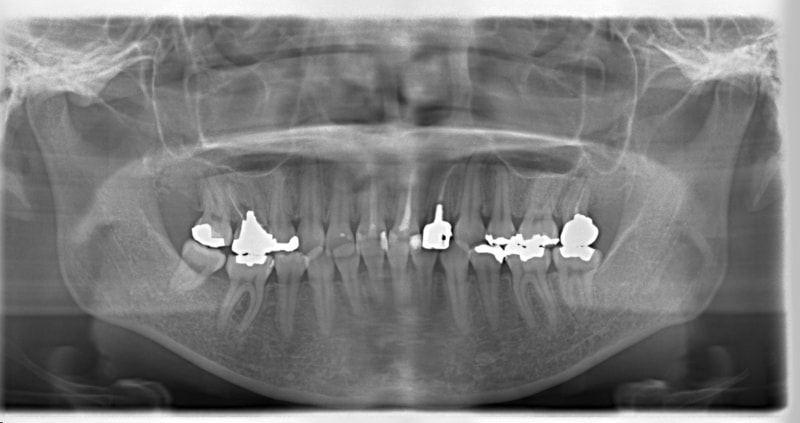

症例紹介

右下7番欠如歯(保存不可能歯につき抜歯)右下8番利用

治療法:フルパッシブブラケット:クリアスナップ

治療前